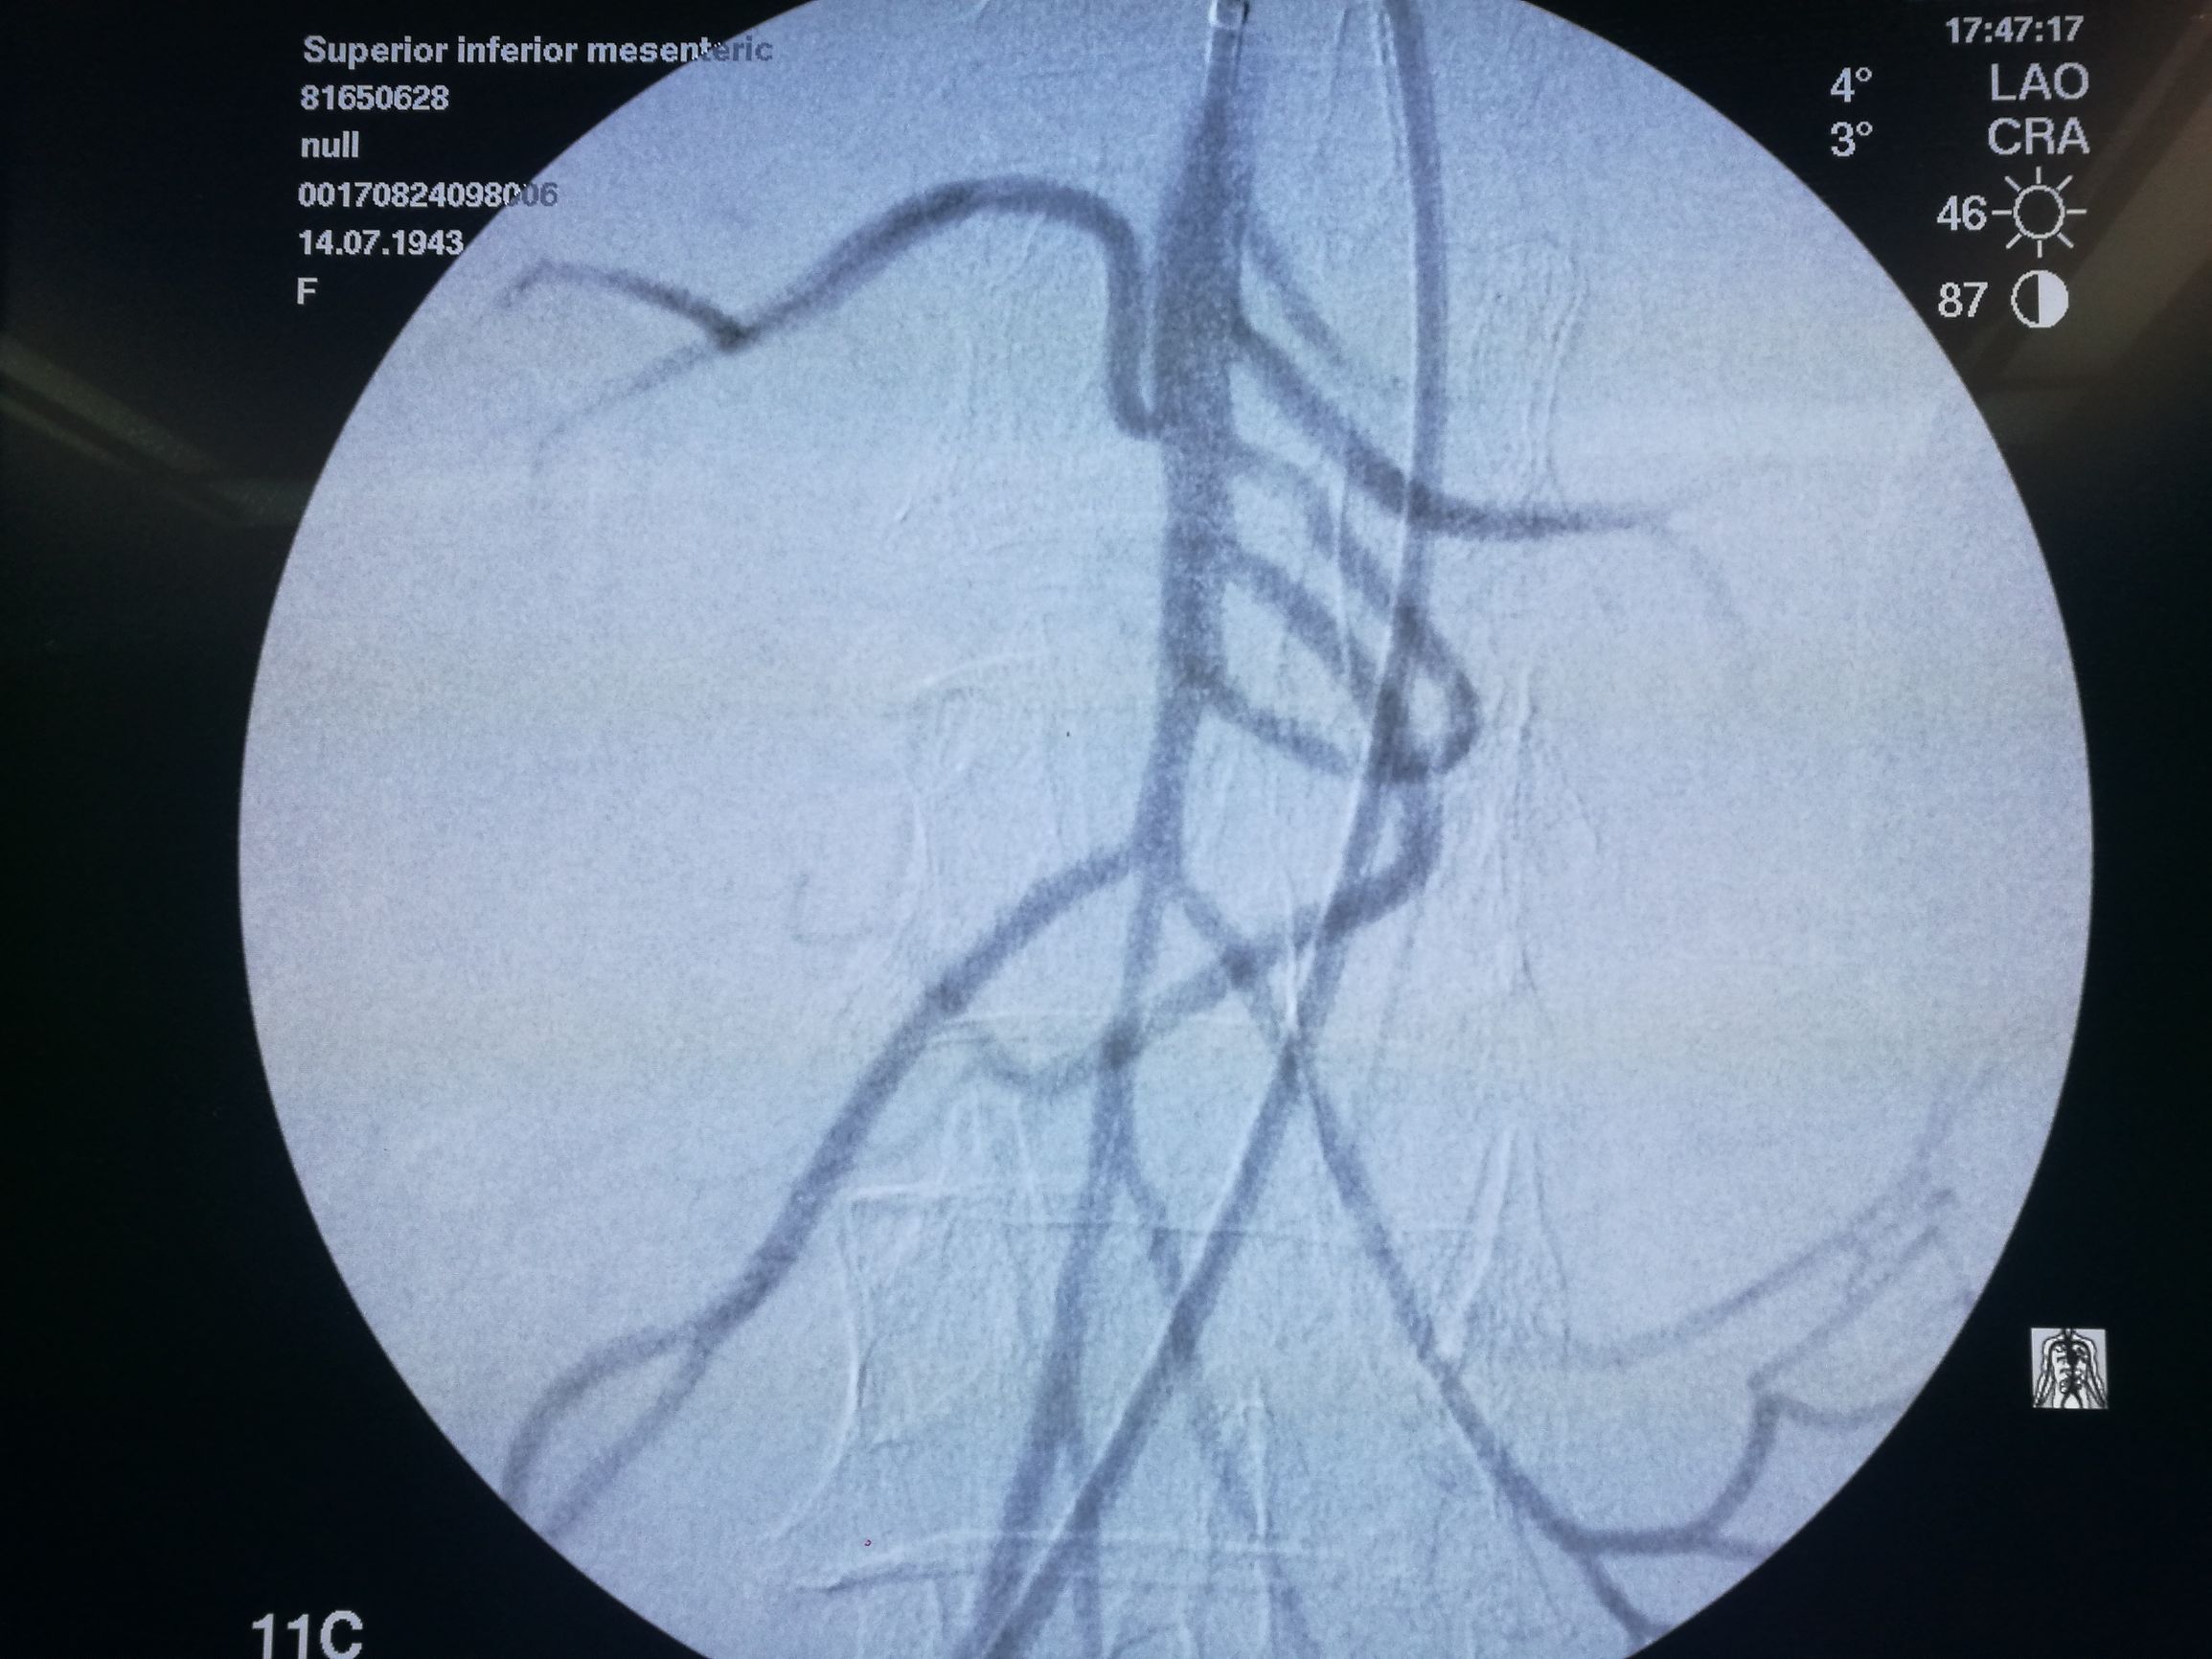

在局麻下经右侧股动脉穿刺,导管选入肠系膜上动脉造影,可见腔内充盈缺损(图3)。

图3. 肠系膜上动脉造影,可见管腔内充盈缺损,局部主干中断

以EV3 SPIDER保护伞取栓(图4)配合6F 指引导管抽吸,取出较多血栓,造影肠系膜上动脉血流通畅